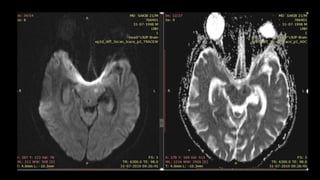

• #118 Sag T1 and axial T2 wi showing T1 hypo and T2 hyperintense foci in left side of pons

• #119 Showing no signal suppression on FLAIR

• #120 With diffusion restriction on DWI and ADC map s/o acute lacunar infarct